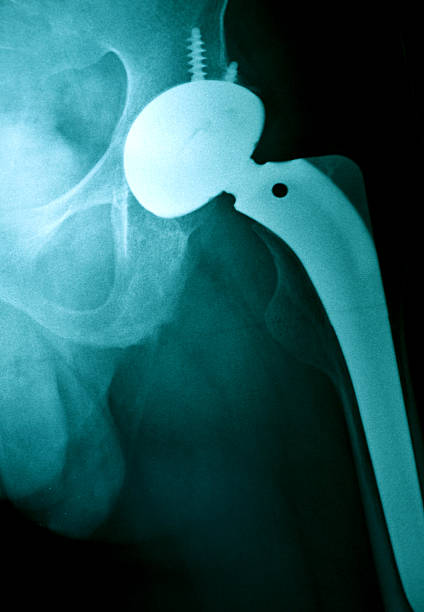

골반 통증 원인 5. 대퇴골두 무혈성 괴사

골반 통증 원인 다섯 번째는 대퇴골두 무혈성 괴사입니다. 이름은 어렵지만 대퇴 골두 무혈성 괴사의 경우 넓적다리 위쪽에서 대퇴 골두로 가게 하는 혈액의 흐름을 차단하기 때문에 뼈 조직이 죽으며 엉덩이 부위와 골반 통증을 유발하는 질병입니다. 따라서 괴사가 발생하더라도 초기에는 아무런 증상을 느낄 수 없다는 점이 특징이기 때문에 조금의 통증이라도 느껴지면 빠른 진료가 필요하며 심해지면 고관절의 손상으로 이어지게 되어 주의가 필요합니다.